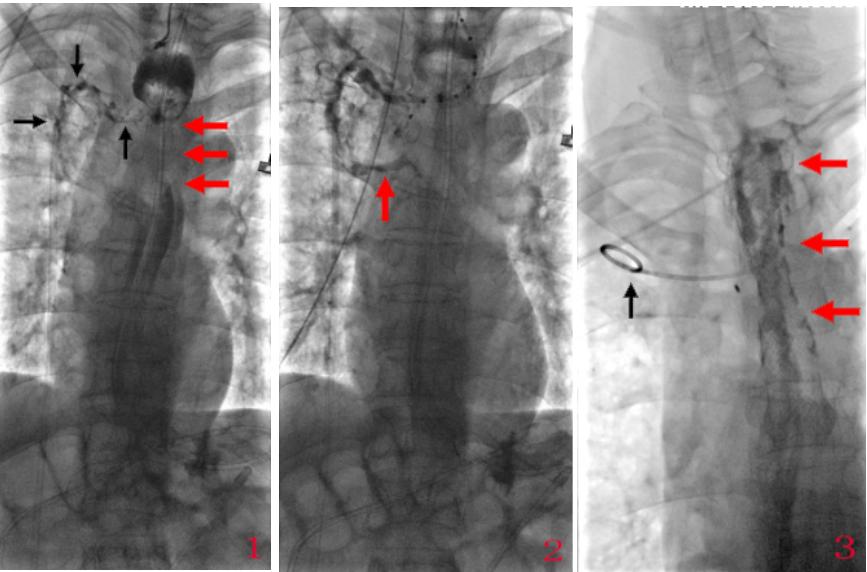

发现病变后,首先要做的是隔绝瘘口,引流脓腔、增加营养措施。DSA下行食管覆膜支架置入+脓腔引流管置入+空肠营养管置入,见下图:

图1示食管回拉造影可见食管上段明显阶段性严重狭窄(红箭头),狭窄上方食管扩张明显,于狭窄上端可见一瘘口,造影剂沿瘘道经纵膈进入右肺上叶,瘘道清晰显影(黑箭头);图2示食道造影后,右主支气管显影(箭头示);图3示于瘘道置入猪尾巴导管(黑箭头)作持续负压抽吸脓液;食道覆膜支架后口服碘水造影瘘口瘘道消失,且造影剂顺利通过食管支架管腔,食管狭窄解除(红箭头)。